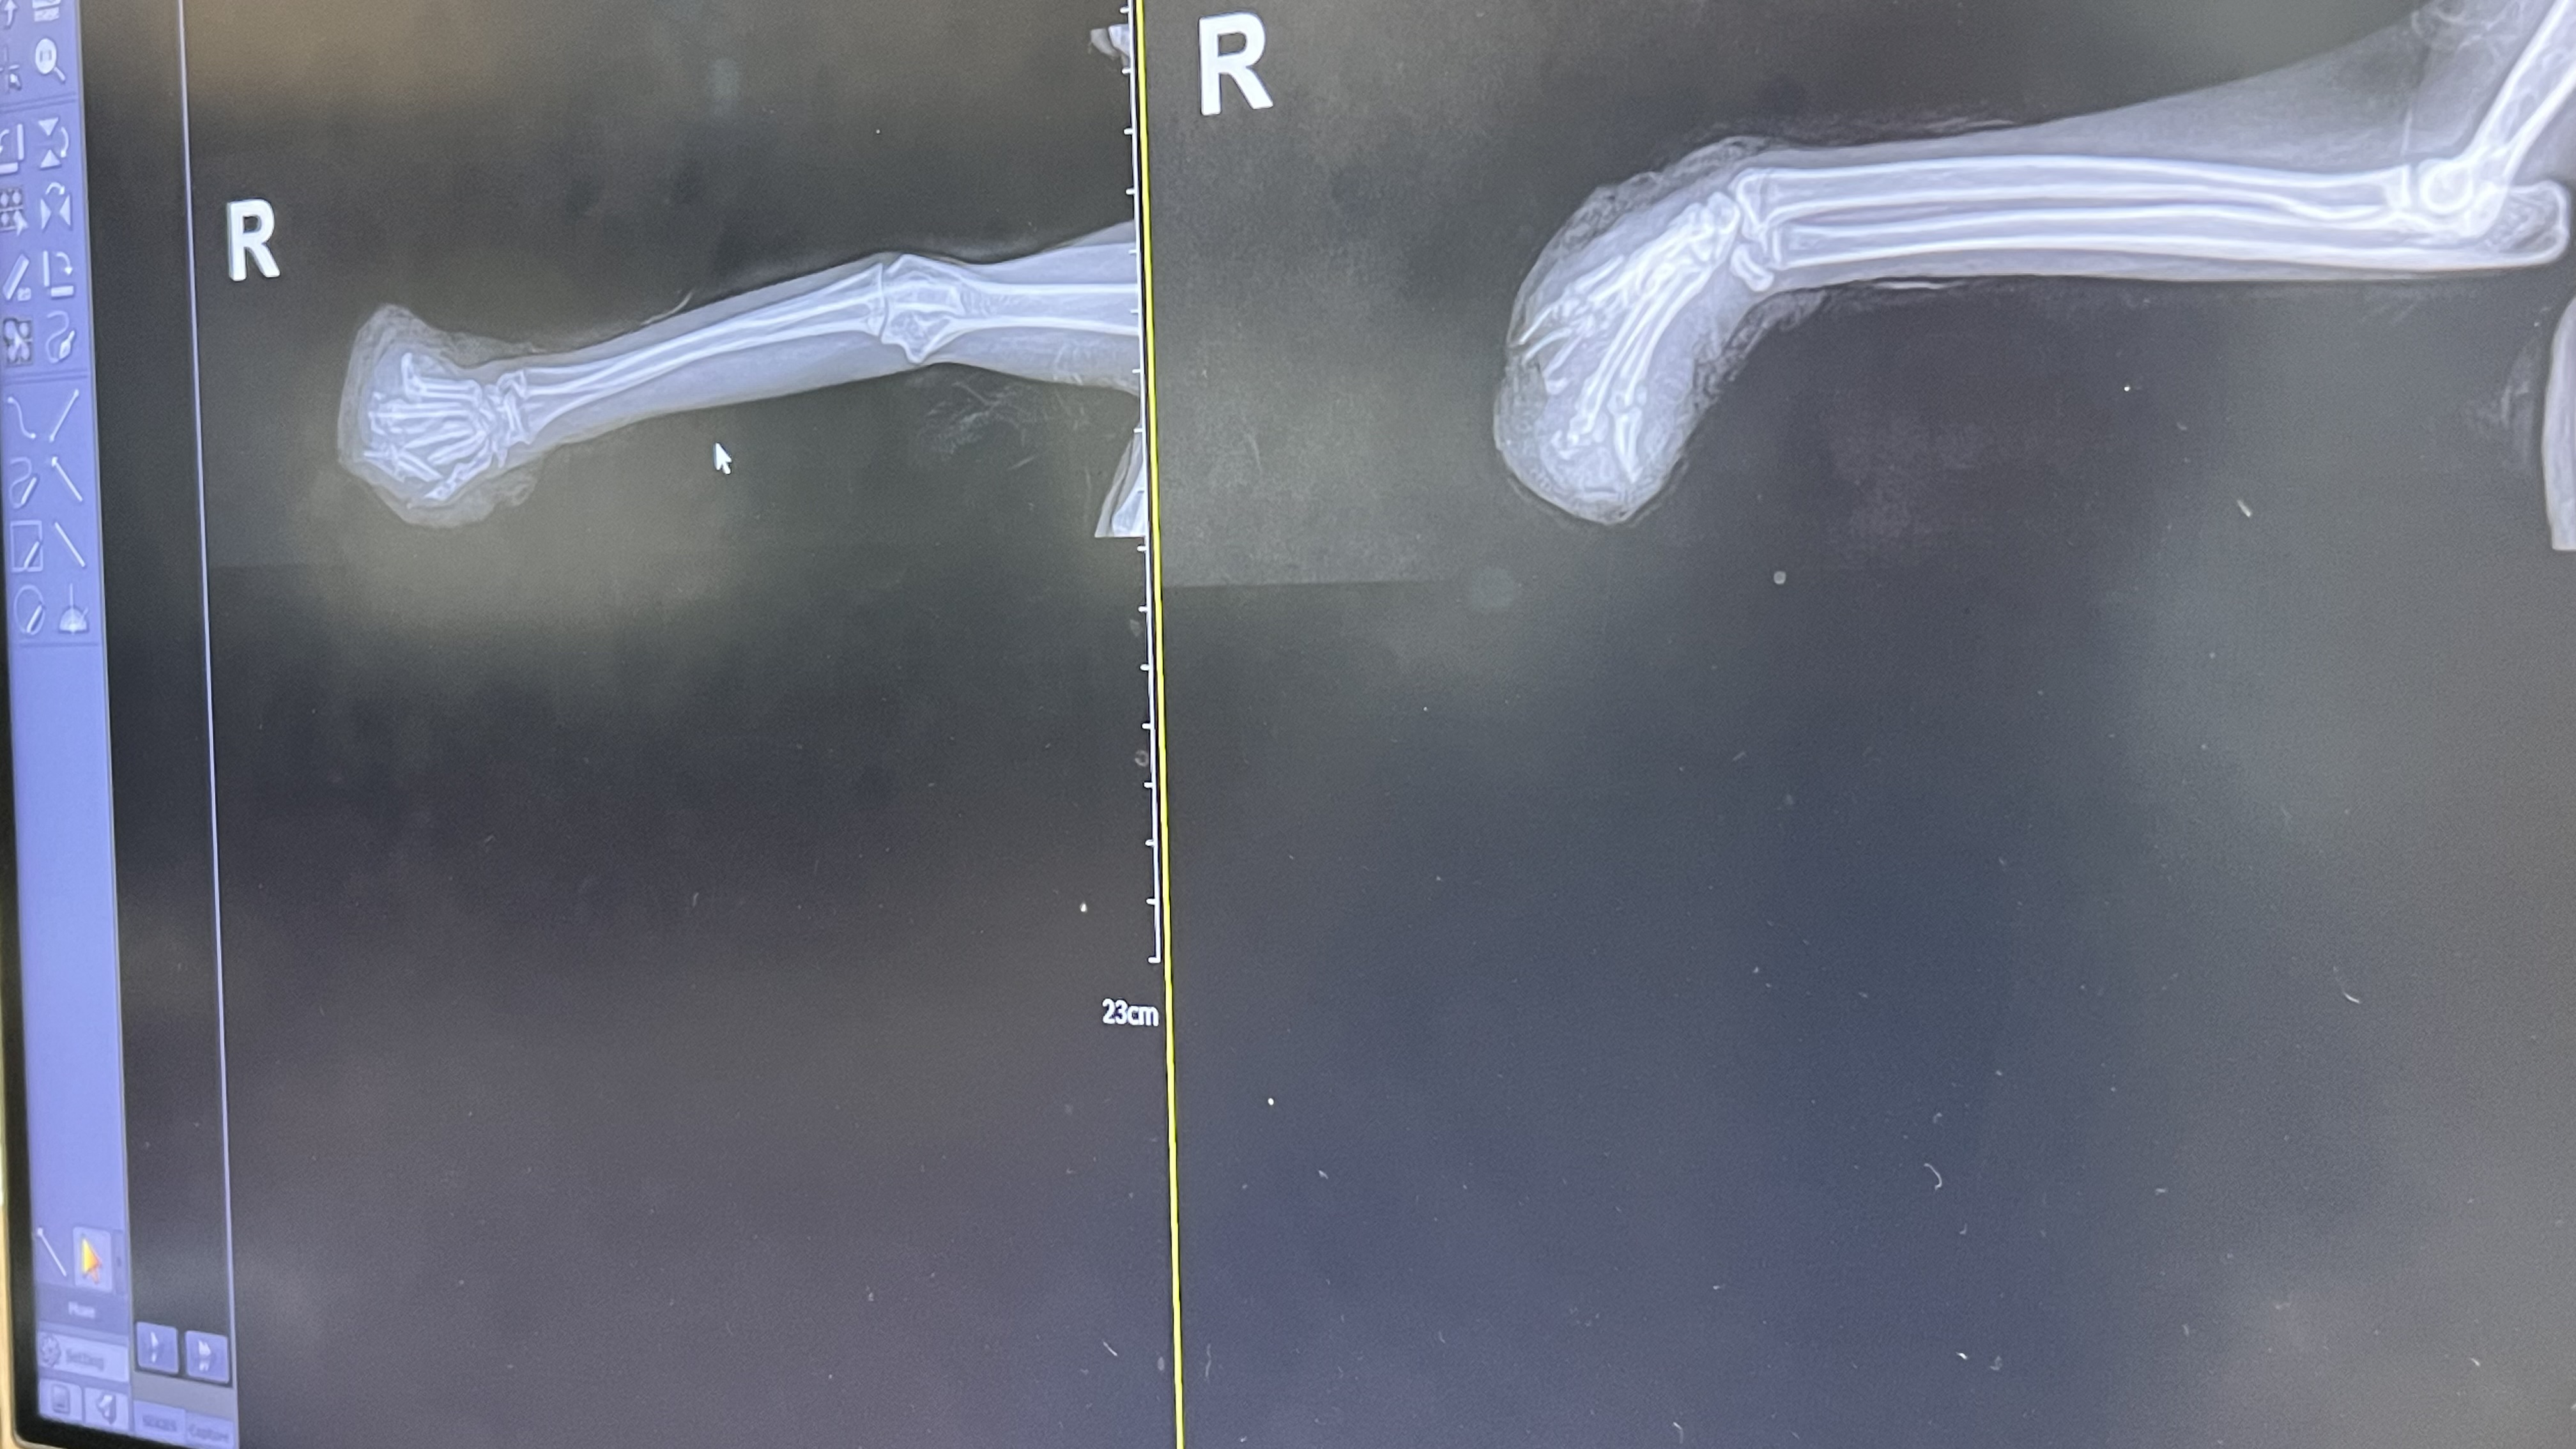

23일에 확실하게 안좋음을 확인하고 25일 아침 7시에 바로 포획하여 병원으로 이동 결과 아이의 발이 다 부러져 조각난 상황이고 염증이 어마 어마하게 부풀어 있는 것으로 보아 시일이 좀 된 것으로 판단된다는 의사쌤의 진단을 들음. 또한 꼬리도 어디선가 상처를 입어 봉합수술이 필요할 정도로 찢긴 상태였음

대상묘 병명 발 전체 부러짐

치료과정 먼저 10월 25일에 여러 시간 상담 후 더이상 발을 사용할 수는 없을 것 같고 워낙 염증이 심해서 발조각을 맞추는 수술은 더욱 어려울 것으로 판단하게 되었음.

결국 한참을 아이의 어깨부터 다리를 절단할 것인지 앞발만 절단할 것인지에 대해 상의했고 성묘이며 오랫동안 발을 사용하던 아이는 어깨부터 다리가 없을 시 추가적으로 문제가 발생할 수 있다는 판단하에 앞발을 절단하는 수술을 감행하였음.

카옹이 치료  사진입니다.

치료 후기에 대해 추가 진행합니다. 카옹이는 발이 으스러진 상태에서 오랜 시간 지연이 되다가 보니 조직이 괴사하고 염증이 발보다 더 큰 상태였습니다. 꼬리 부분도 다른 고양이에게 공격을 받은 것인지 아니면 이 또한 차량에 밟혀서 상처가 생긴 것인지 확실하지는 않지만 상처가 크게 벌어진 상태였습니다. 전반적으로 카옹이는 거의 죽어가고 있었습니다. 만약 구조하기로 한 날 구조가 되지 않았다면 카옹이는 죽었을 것 같다고 하더라구요.  의사 선생님의 가장 큰 고민은 아이의 발을 어깨부터 자를 것인지 발목만 잘라도 될 것인지였는데 결국 선택은 발목 절단 수술이었습니다. 카옹이가 이미 성묘였기 때문에 어깨부터 다리를 잘랐을 경우 자칫 다리가 아직 있다는 느낌을 계속 가지고 갈 수 있고 그러다가 다리가 수술을 했음에도 불구하고 계속 아프다는 느낌을 가져가는 경우도 있다고 하더라구요. 게다가 걸을 때도 다리 전체가 없는 것과 발목만 없는 것은 어마어마한 차이가 있구요. 수술이 잘 끝나고 쎈 진통제를 계속 수액과 함께 맞으면서도 많이 아픈지 제대로 먹지도 않고 엄청나게 공격적이었습니다. 오죽하면 카옹이 입원장 앞에 흰색 글씨로 '매우 사나우며 튀어 나올 수 있음'이라고 써 있었겠어요. 하지만 약 2주가 지나고 어느 정도 회복이 되면서 카옹이는 엄청나게 착한 원래의 성격으로 되돌아와 있었습니다. 카옹이의 무사 수술과 치료에 대해 너무 너무 감사하는 마음입니다.

IMG_9207.JPG

IMG_9208.JPG

IMG_9209.JPG